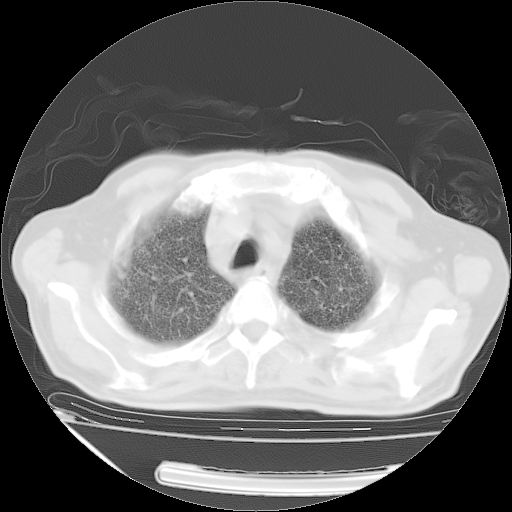

甲强龙80mg/日+抗结核治疗(异烟肼+利福霉素+乙胺丁醇)10天。复查肺部CT。

治疗10天肺部CT

仔细阅读病史资料和CT,我觉得两肺粟粒结核要高度怀疑。

今天带四次肺CT片到市医院,影像科4~5个主任都认为不考虑粟粒性肺结核。主要理由是在3月19日、4月2日、4月27日的CT片没有见到确切异常(肺结核)影像。影像科主任们建议找呼吸内科主任,呼吸内科主任认为首先考虑粟粒性肺结核。